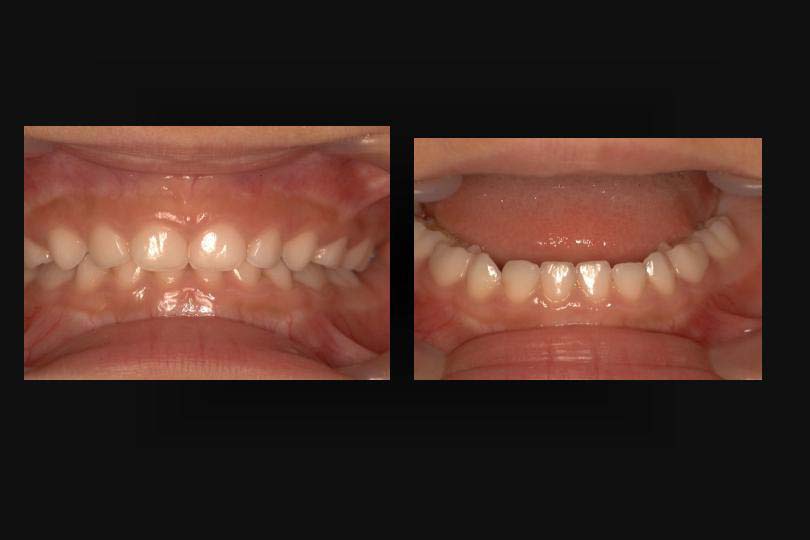

また乳歯の下顎前歯に叢生が認められる小児も、過蓋咬合が多い。(図2)

図2

一方、閉鎖型歯列弓では、下顎の永久側切歯は中切歯より大きく写っている。

これは下顎の中切歯より、側切歯が舌側にあることを意味している。(図6)

図6

図2:乳歯なのに叢生の場合、過蓋咬合であることが多い。

図6:乳歯の閉鎖型歯列弓は、下顎永久側切歯は、舌側へ萌出する可能性が高い。